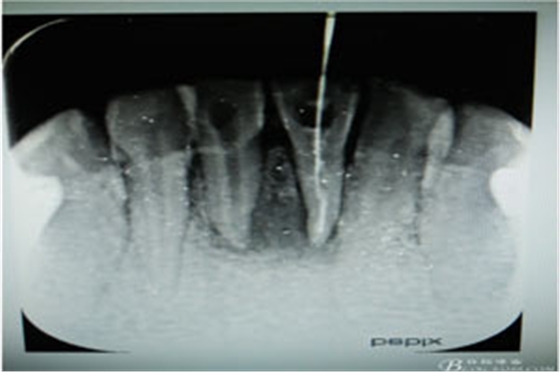

圖3.術(shù)中x線片檢查:31預(yù)備植根中1/3與根尖1/3遇阻力,根管測量無法測到長度,根尖1/3牙膠無法取出。

圖5.31、41試主尖,發(fā)現(xiàn)31根尖1/3有外吸收,糊劑有外溢現(xiàn)象。